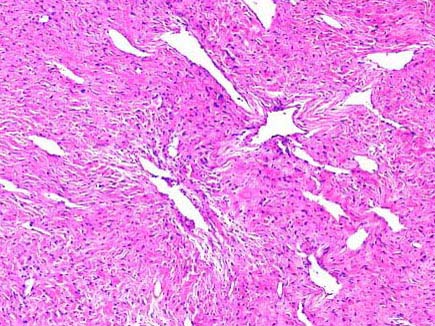

患者,男,18岁,鼻塞、鼻出血,鼻腔镜检查见一鲜红色圆形肿物凸向鼻腔,约2cm×1cm×0.5cm大小,表面光滑,活检如图1、2所示,正确的诊断是 ( )

• E.鼻腔纤维血管瘤